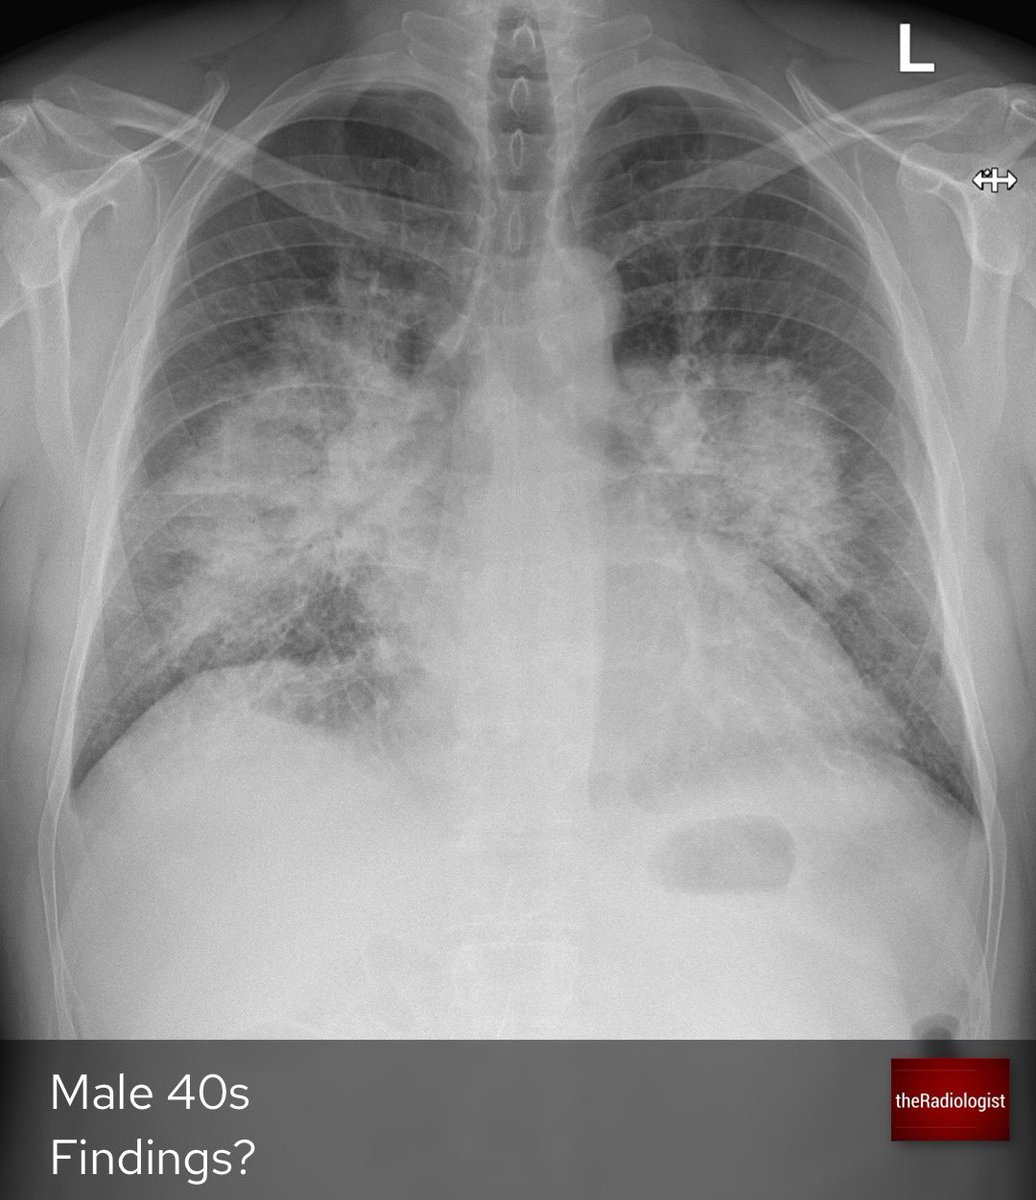

Bat Wing Appearance On Chest X Ray Pulmonary Edema On Chest

Pulmonary Oedema Chest X Ray MedSchool

Bat s Wing Or Butterfly Pulmonary Opacities Refer To A Pattern Of